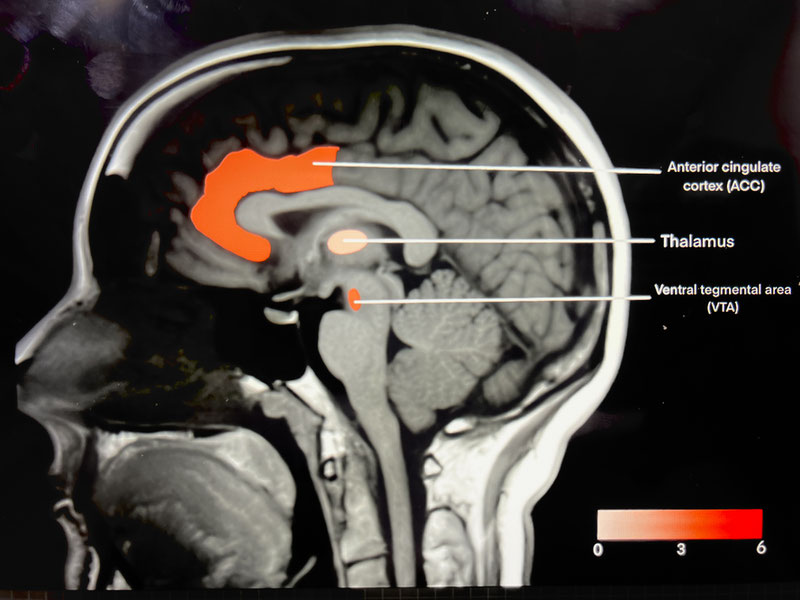

Analyzing MRI Scans to Detect Different Levels of Alzheimer’s Disease

I created an app which you can input an image of an MRI scan of a brain and it will output the severity level of Alzheimer’s detected from the MRI scan

Alzheimer’s Disease and Advanced Research Therapy

My research is on Alzheimer' and its advanced research Therapy, Alzheimer' is a very devastating disease which has no cure, but there are new treatments to lower the Risk of symptoms of Alzheimer' I this research I also look into the mechanisms.